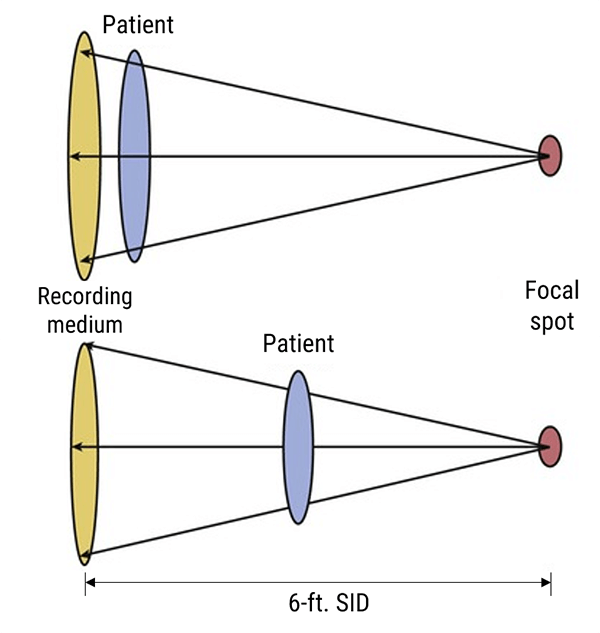

X-rays travel in straight lines in air at a distance of 72 inches from the detector. They diverge in all directions and are attenuated by the housing around the cathode ray tube and by the collimator filters. The structures that the beam hits first, will be magnified in relation to those which are nearer the detector.

Three terms are used to describe positioning: source-object distance SOD, where the object represents the patient; object-image distance OID, where the image is the detector; and source-image distance SID.

To represent an image with as little magnification as possible, the X-ray tube should be placed 72 inches from the image receptor.

X-ray images are shadows of the anatomy represented on the image receptor. The farther the object is from the image receptor, the more magnified it becomes.

The method of similar triangles is used to show the effects of moving the patient and the detector. To reduce magnification the X-ray source can be moved further away from the patient. Organs that need to be measured accurately, should be placed closer to the detector.